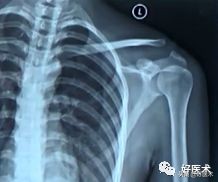

- X线照片:左侧:术前;右侧:术后

- X线照片:左侧:健侧;右侧:患侧术后